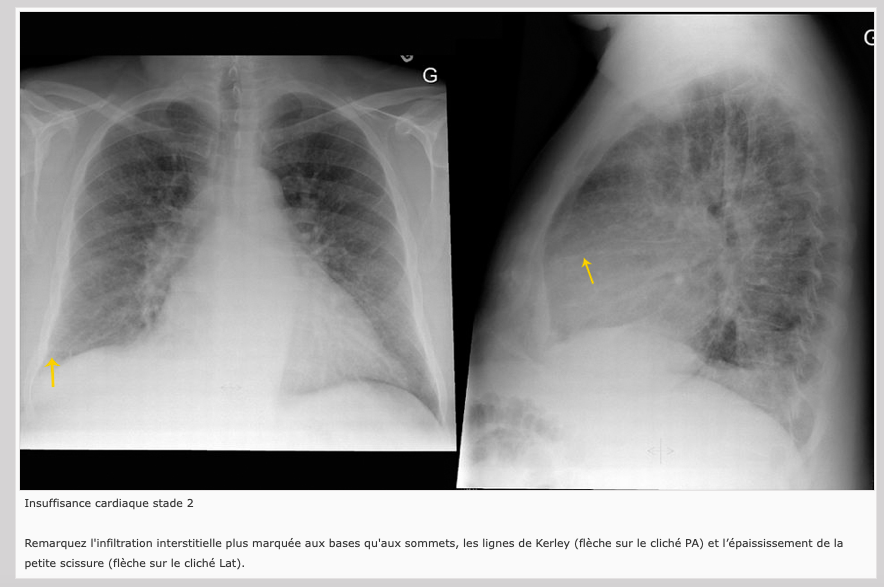

2) Odème interstitiel:

Infiltration interstitielle plus marquée aux bases (Lignes de Kerley)

Épaississement péri-bronchique

Épaississement des scissures